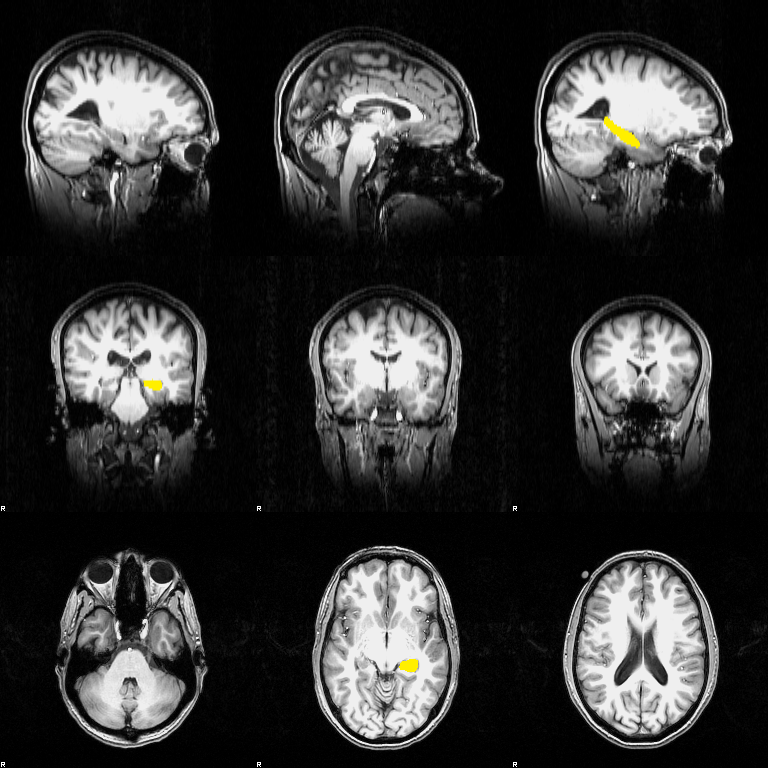

FIRST

First you must register your data to standard space; in a terminal type:

first_flirt structural structural_to_std_sub

(structural, structural_to_std_sub images.) Now run a single structure's segmentation; type:

run_first -i structural -t structural_to_std_sub.mat -n 20 -o structural_first_L_Hipp -m \ ${FSLDIR}/data/first/models_317_bin/L_Hipp_bin.bmv

(${FSLDIR}/data/first/models_317_bin/L_Hipp_bin.bmv image.)